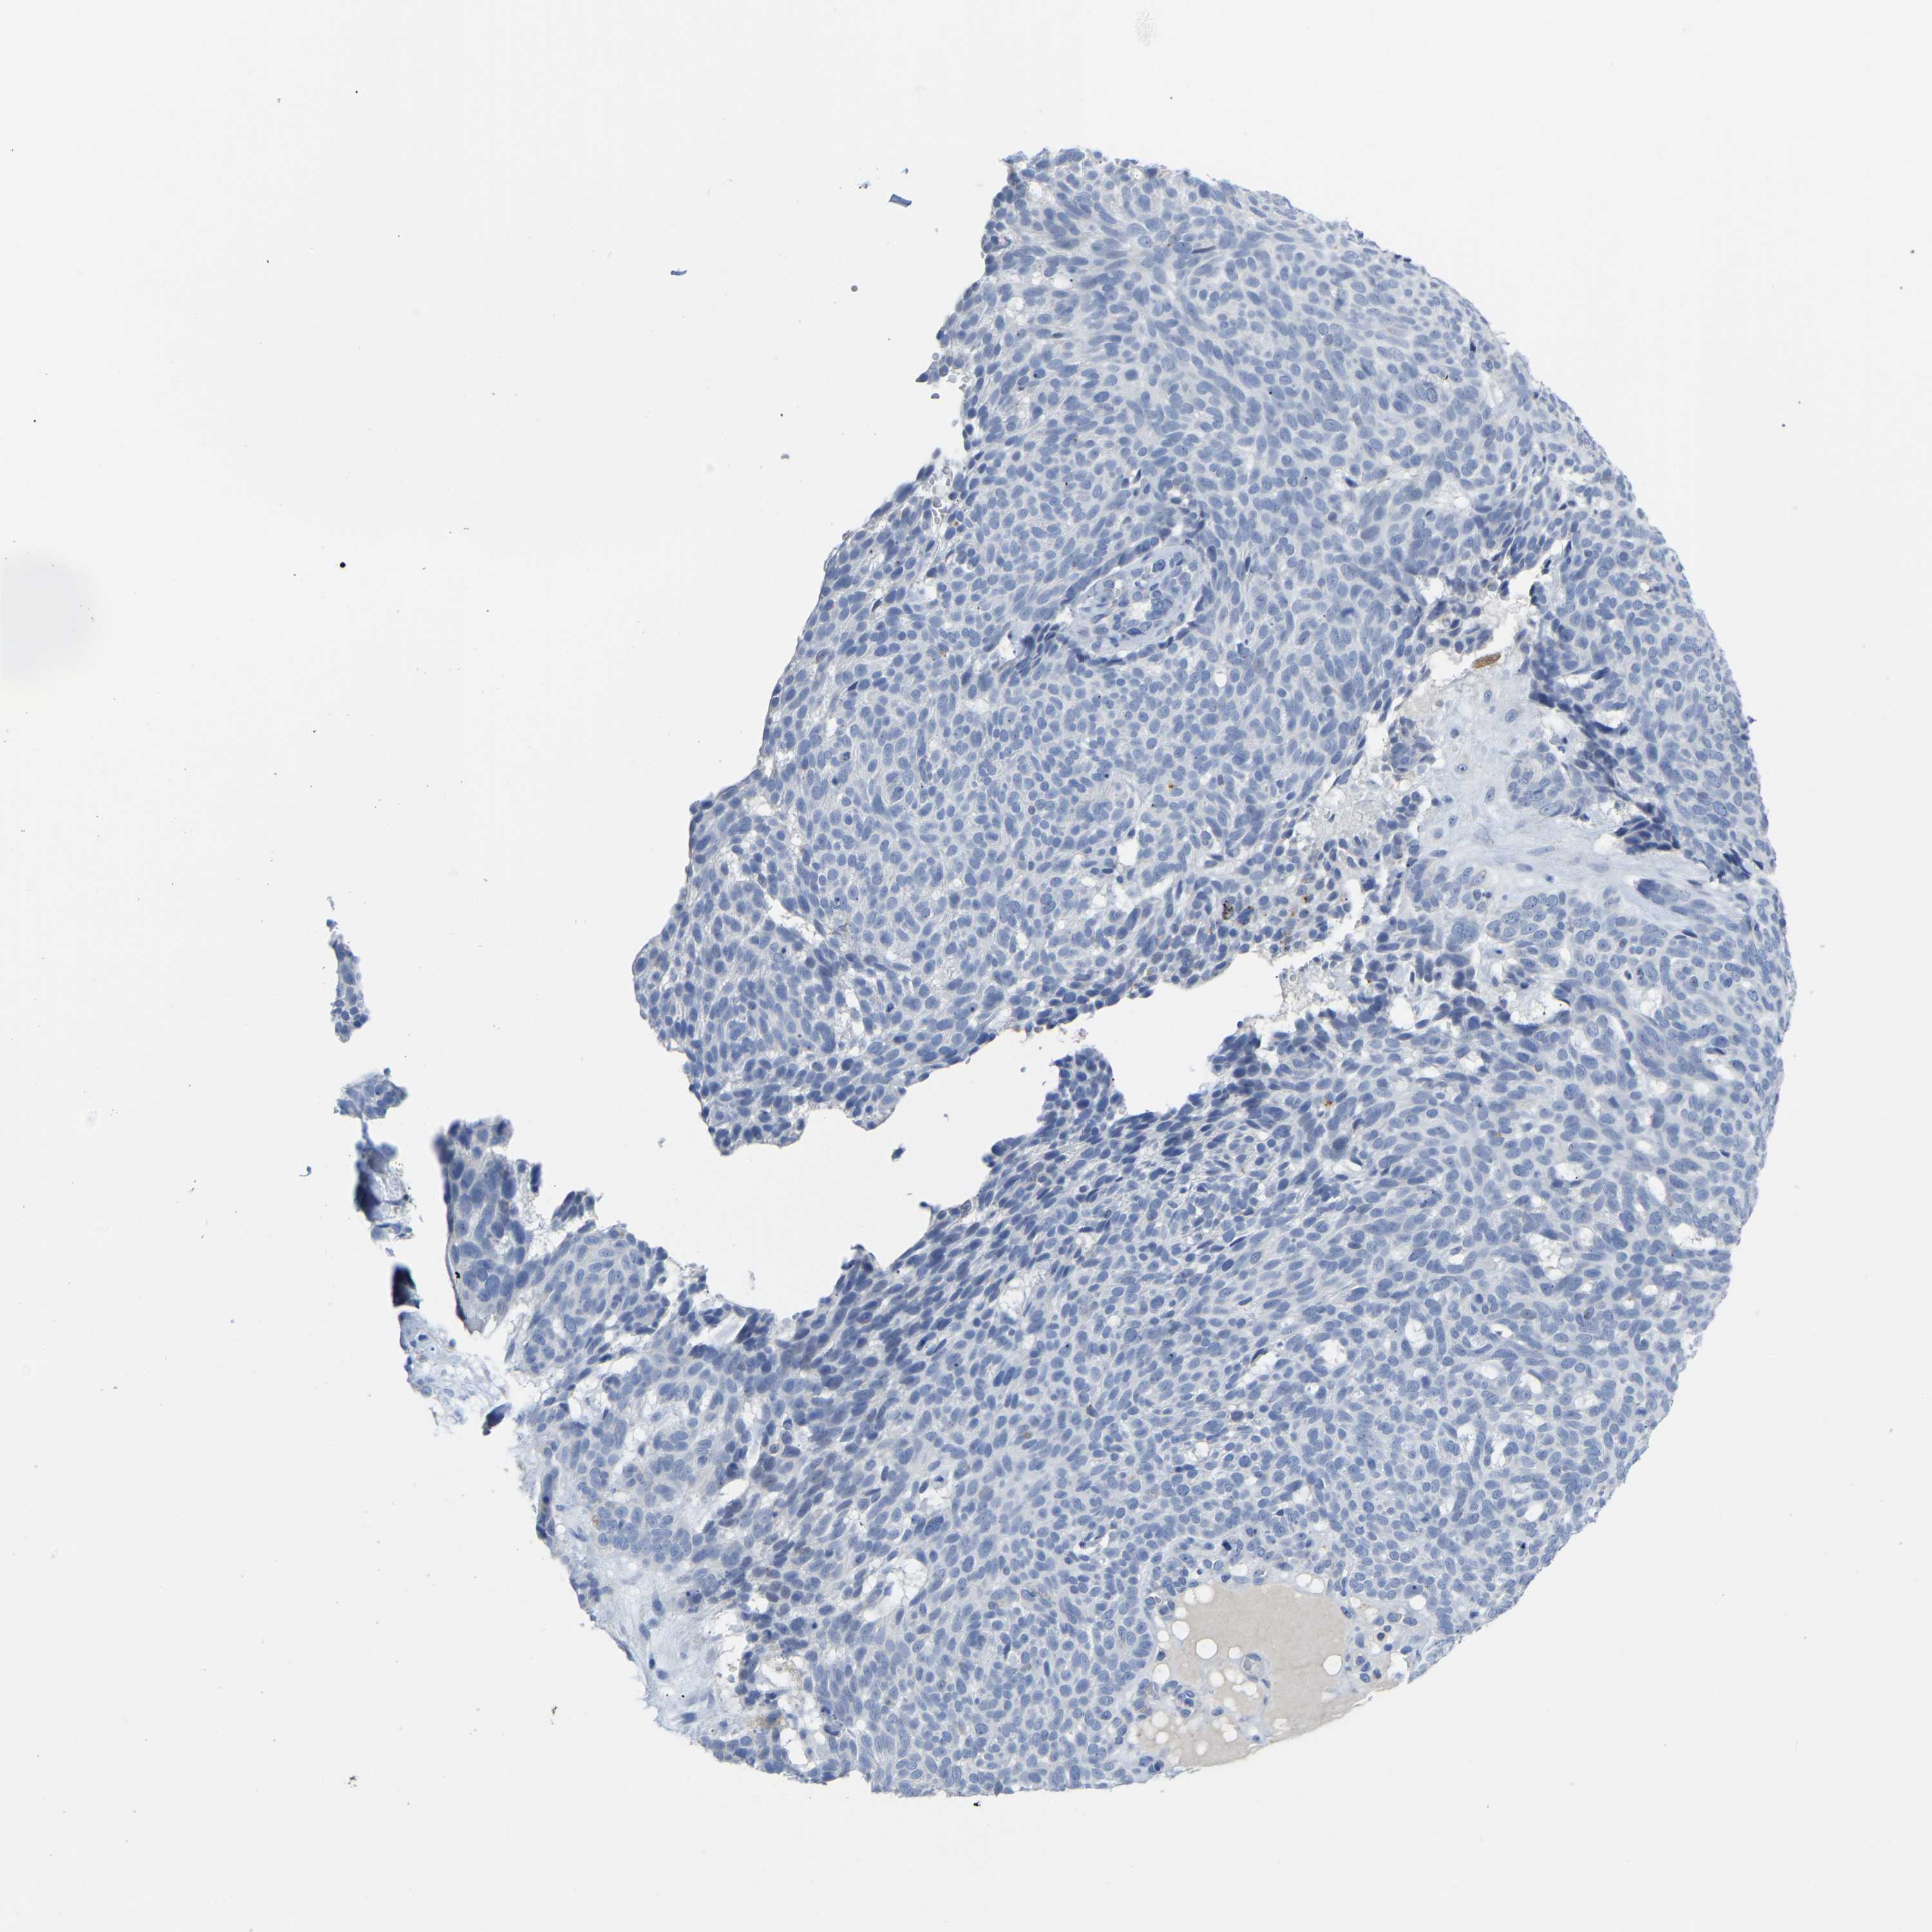

SKIN CANCER - Protein expressioni

A mouse-over function shows sample information and annotation data. Click on an image to view it in a full screen mode. Samples can be filtered based on level of antibody staining by selecting one or several of the following categories: high, medium, low and not detected. The assay and annotation is described here.

Each image is clickable and will lead to virtual microscopy that enables deeper exploration of all samples and also displays staining intensity scores, fraction scores and subcellular localization as well as patient and tissue information for each sample.

Antibody HPA024089

Squamous cell carcinoma, NOS